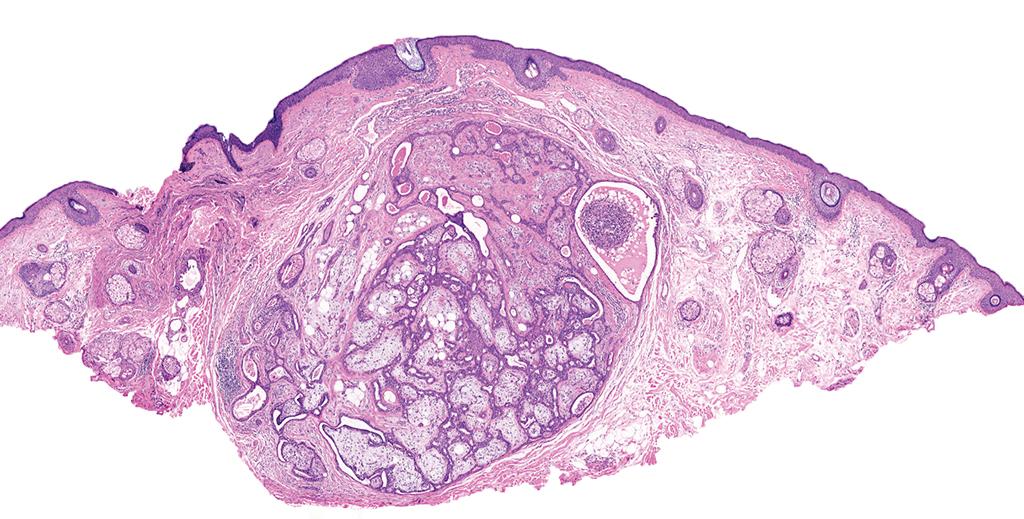

✅ Mixed tumor 🎯🍹

• Biphasic sweat gland neoplasm with epithelial and mesenchymal elements.

• Features branched tubules or round ducts set in a myxoid, chondroid, or osseous stroma.

• Most apocrine-pattern cases harbor a diagnostic PLAG1 rearrangement.

• Also known as chondroid syringoma, it is the cutaneous analog of pleomorphic adenoma.

#PathQuiz 🔬 #DermPath

A) Mixed tumor

B) Myoepithelioma

C) Syringoma

D) Hidradenoma

#Pathology #DermPath